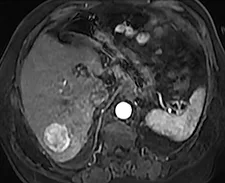

La cicatrice de thermoablation se présente sous forme d’une image nodulaire avasculaire, spontanément hyper intense T1 avant injection, en rapport avec la nécrose de coagulation (figure 2).

Une récidivé loco-régionale se présente sous forme de prise de contraste nodulaire sur les berges de cette cicatrice. Les séquences en pondération T2 ou en diffusion pour diagnostiquer la récidive sont plus difficiles à interpréter car il persiste longtemps après le geste une hyper intensité T2 au sein ou au pourtour de la cicatrice.

| Contrôle en IRM après radiofréquence multibipolaire : la cicatrice de thermoablation apporte des marges centimétriques, est totalement avasculaire aux différents temps de l’injection (artériel et portal). | |